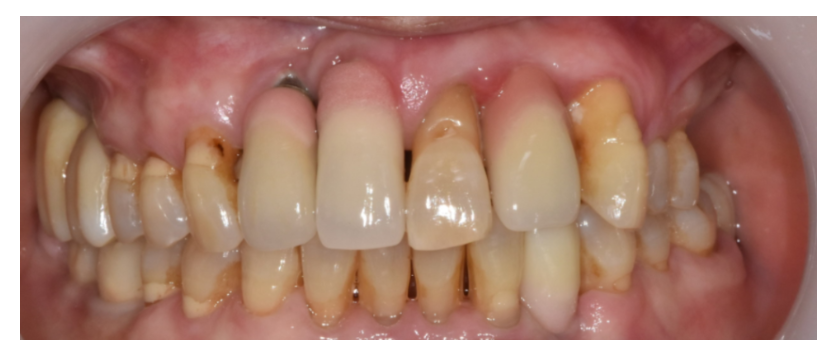

240508 눈에 보이는 보철 상태

머리 부분이 비어보이지 않게 당일

임시치아까지는 가능할 수 있습니다.

240429 하루만에 임플란트는 때문에 앞니에 많이 진행합니다.

힘을 많이 받지 않아도 되기 때문이죠.